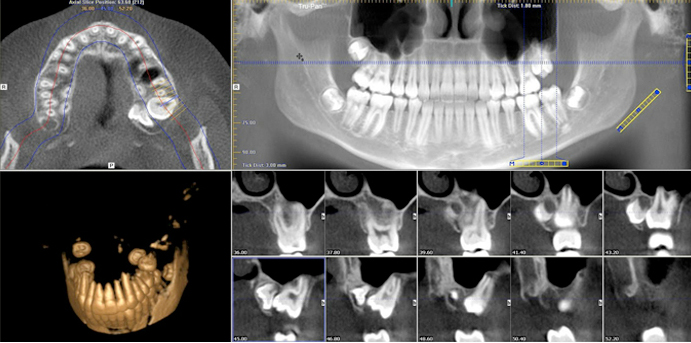

Il Dentalscan o Tac dentale valuta la condizione generale delle arcate dentarie in caso di impianti ed estrazioni dentali. È uno strumento digitale con immagini tridimensionali per poter elaborare la ricostruzione dentale, per agevolare il programma di ricostruzione e coadiuvare l’opera del dentista che potrà modificare le operazione tridimensionali (misurazioni) a suo gradimento.

Un approccio del tutto nuovo alla disciplina odontoiatrica resa possibile dalla più elevata tecnologia della diagnostica per immagini digitale in 3D Cone Beam (tomografia computerizzata). Il clinico che approccia alla definizione di un piano terapeutico (Il field of view Fov) deve infatti poter reperire tutte le informazioni anamnestiche e diagnostiche utili alla definizione della stessa. I principi di ottimizzazione e giustificazione a cui si deve ispirare il professionista non dovranno essere inficiati da limiti tecnologici legati alle apparecchiature usate, che dovranno quindi offrire tutte le possibilità diagnostiche necessarie senza alcun compromesso: ed è proprio questa la mission del Dentalscan.

La tecnologia Dentalscan Cone Beam 3D (Tomografia Computerizzata) è utilizzata per svolgere esami radiodiagnostici sofisticati applicati nel campo dell’implantologia moderna. La tecnologia Cone Beam è in grado di svolgere scansioni delle arcate dentali mediante una bassa dose di raggi X, sottoponendo quindi il paziente ad un esame ancor più sicuro per la propria salute.

Lo scanner del macchinario Dentalscan Cone Beam, effettuando una rotazione intorno il paziente, è in grado di produrre, nel giro di pochi secondi, centinaia di immagini che il sofware elaborerà per restituire le immagini 3D delle zone maxillo-facciali esaminate.